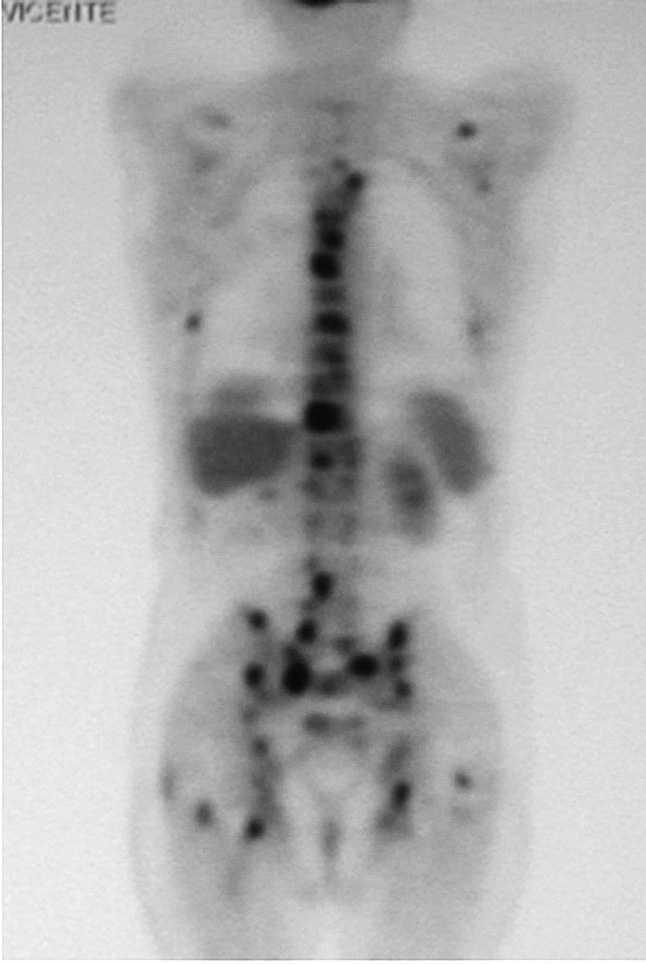

Un varón de 76 años acudió al hospital por fiebre y disfonía. Quince años antes había sido intervenido quirúrgicamente, tras sufrir la rotura de un aneurisma de la aorta abdominal, realizándose una endoaneurismorrafia y un injerto aorto-bifemoral. Dos meses antes había ingresado por presentar una miositis abscesificada en muslo derecho que precisó drenaje quirúrgico. La exploración era anodina a excepción de las secuelas de las intervenciones quirúrgicas previas y la disfonía. Entre los datos analíticos destacaba la existencia de leucocitosis (11.600/ml) con neutrofilia, anemia (Hb: 10 g/dl) normocítica normocrómica, elevación de la velocidad de sedimentación globular (VSG) (60 mm/ primera hora) y aumento de la lacticodeshidrogenasa (LDH) (604 UI/l). El urinocultivo fue negativo, mientras que en los hemocultivos creció una Escherichia coli. En el examen otorrinolaringológico se observó la existencia de una parálisis de la cuerda vocal derecha. La radiografía de tórax mostraba signos de hipertensión arterial pulmonar y atrapamiento aéreo. La tomografía computarizada (TC) de cuello y tórax puso de manifiesto la existencia de un nódulo de 1,3 cm de diámetro en lóbulo superior derecho (LSD), que hacía contacto con la pleura de la pared torácica posterior. En la gammagrafía ósea con 99mTc se observaron varios focos hipercaptadores en parrilla costal izquierda y esternón, así como un patrón heterogéneo irregular en la columna vertebral. La tomografía por emisión de positrones (PET/ TC) reveló la existencia de captación sugestiva de malignidad en el nódulo pulmonar del LSD (fig. 1), en los ganglios mediastínicos, glándula suprarrenal izquierda y parénquima hepático, así como múltiples focos hipercaptantes en el esqueleto compatibles con una diseminación ósea metastásica (figs. 2, 3 y 4). En las citologías de esputo y en el aspirado bronquial se observaron células atípicas sugestivas de carcinoma no microcítico (carcinoma indiferenciado).

Fig. 2. Tomografía por emisión de positrones con fluorodesoxiglucosa (PET-FDG), corte coronal, en el que se aprecia la diseminación tumoral ósea, hepática y la afectación de la glándula suprarrenal izquierda. A: proyección anterior. B: proyección posterior.